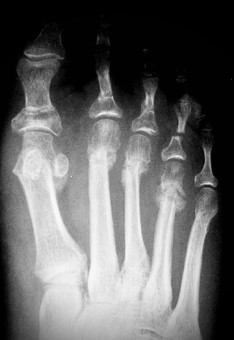

Al mes se programó una radiografía y si había suficiente callo fibroso se le dio la opción a la paciente de usar otro tipo de zapato, pero siempre de suela ancha y dura (Figura 3).

Figura 3a

Figura 3b

Figura 1. Evolución radiográfica de metatarsalgia aislada, radiografía dorso – plantar a) preoperatoria, b) postoperatoria, c) al año de la intervención